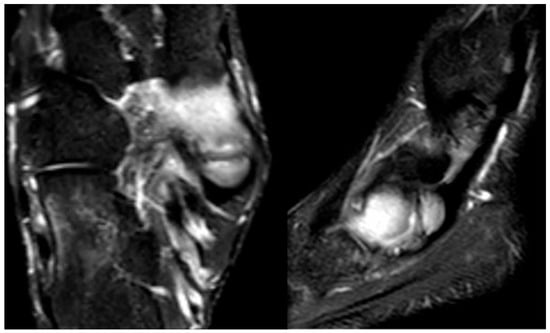

In the later stages, radiographs may reveal characteristic changes including subchondral sclerosis, fragmentation, and flattening of the affected metatarsal head (Figure 10 and Figure 11). In some cases, the presence of joint space narrowing or bony irregularities may also be observed. However, early changes, such as bone marrow edema or subtle cartilage damage, may not be visible on standard radiographs. MRI is particularly useful in the early stages of the disease, as it can detect bone marrow edema, which is a sign of active bone inflammation and necrosis, even before structural changes become apparent on radiographs (Figure 10, Figure 11 and Figure 12).

Figure 10.

Radiograph (left) and MRI (right) of a 17-year-old female patient showing necrotic changes and initial flattening of the second metatarsal head.

Figure 11.

Radiograph (left) and MRI (right) of a 15-year-old male patient with osteochondrosis of the third metatarsal head and early signs of deformation.